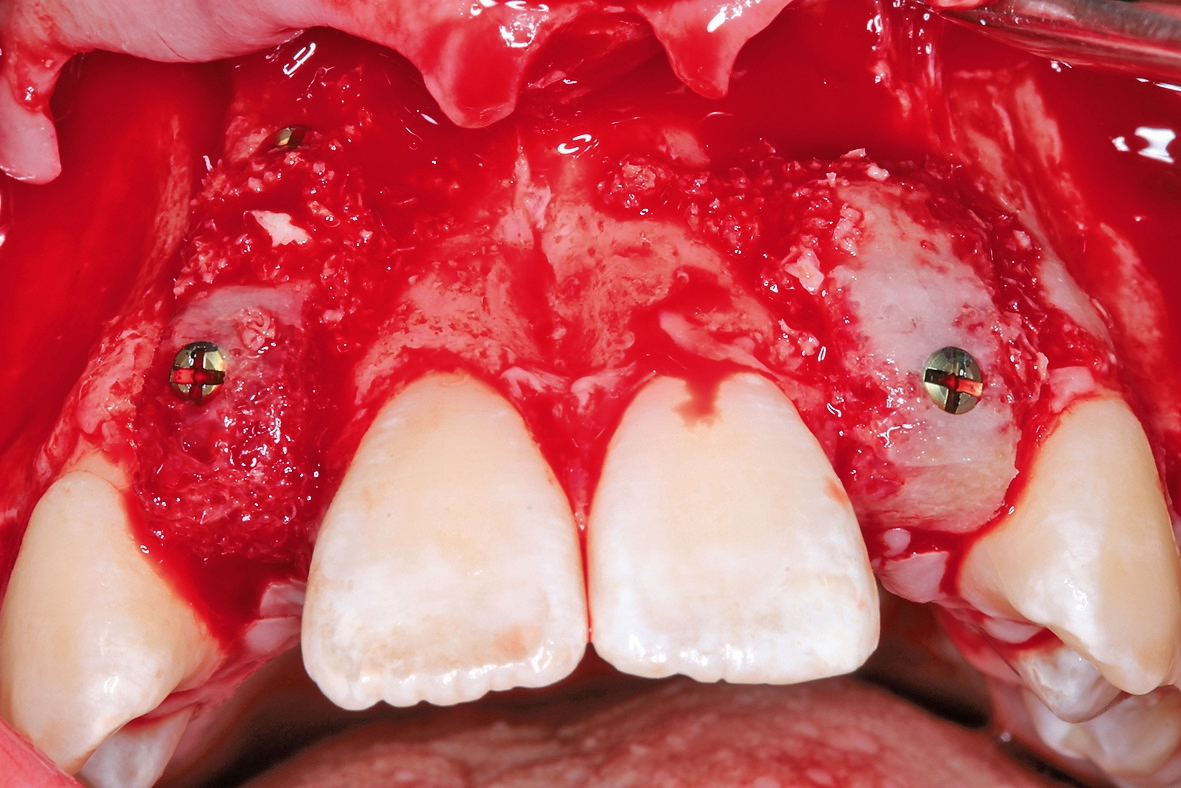

Letztendlich bestand aus kieferorthopädischer Sicht keine Kontraindikation für eine unverzügliche chirurgische Intervention mit nachfolgender implantatprothetischer Versorgung bei derart fortgeschrittener horizontaler Atrophie in regio 12 und 22 (2,5 mm mit großer Konkavität). Insofern wurde nach erneuter intensiver dokumentierter Beratung und Aufklärung wie auch wirtschaftlicher Aufklärung nach entsprechender beidseitiger Leitungsanästhesie am Foramen infraorbitale und zusätzliche intraoralen und vestibulären Infiltrationsanästhesien zunächst ein breiter Mukoperiostlappen von regio 14 bis 24 gebildet (Abb. 4) und zur Förderung der Durchblutung des allogenen Transplantates wurden entsprechende Bleeding-Points (entsprechende Perforation der bukkalen Kortikalis) gesetzt (Abb. 5). Die mit Hilfe von CAD/CAM durch das Labor ProDent (Zahntechnikermeister Thomas Blaschke) hergestellten kortikospongiösen Blöcke nach DVT-Auswertung wurden mit entsprechenden Osteosyntheseschrauben fixiert (Abb. 6) und mögliche Restspalträume mit allogener Spongiosa abgedichtet und lateral auskonturiert.

Nach viereinhalbmonatiger Einheilung der allogenen Knochenblöcke wurde wiederum ein Mukoperiostlappen mit einseitigem vertikalen Entlastungsschnitt gebildet und die Implantate prothetisch nach korrekter prothetischer Planung mit Hilfe einer Schablone in regio 12 und 22 inseriert (Abb. 9 und 10). Zur erneuten Auskonturierung wurden allogene Knochenspäne bukkal unter den Mukoperiostlappen geschoben und zur Weichgewebsaugmentation eine erneute autologe L-PRF-Membran nach Choukroun appliziert (Abb. 11 und 12). Abbildung 13 zeigt das postoperative OPG nach Insertion der beiden Implantate. Zur provisorischen Versorgung erhielt die Patientin wiederum beidseitig eine palatinal verklebte Maryland-Brücke regio 12 und 22.